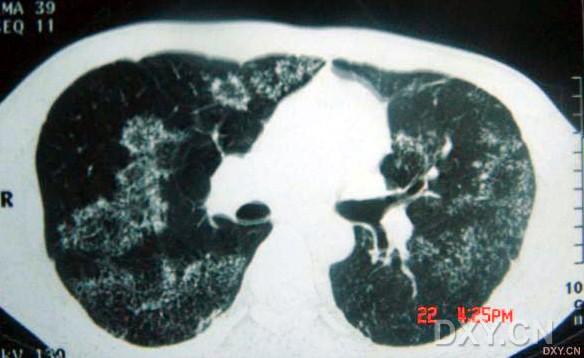

影像表現(xiàn):

兩肺彌漫性顆粒狀陰影,部分陰影融合呈團塊狀,可見支氣管氣相;

呈非對稱,非均勻分布性,部分肺野呈磨玻璃密度;

多處胸膜局限性增厚,胸水征(--)縱隔窗為正常。

臨床表現(xiàn)提示為非細菌性感染性疾病,ct表現(xiàn)為以肺泡實變?yōu)橹鞯膹浡躁幱埃?/font>

病理結(jié)果為:過敏性肺泡炎。